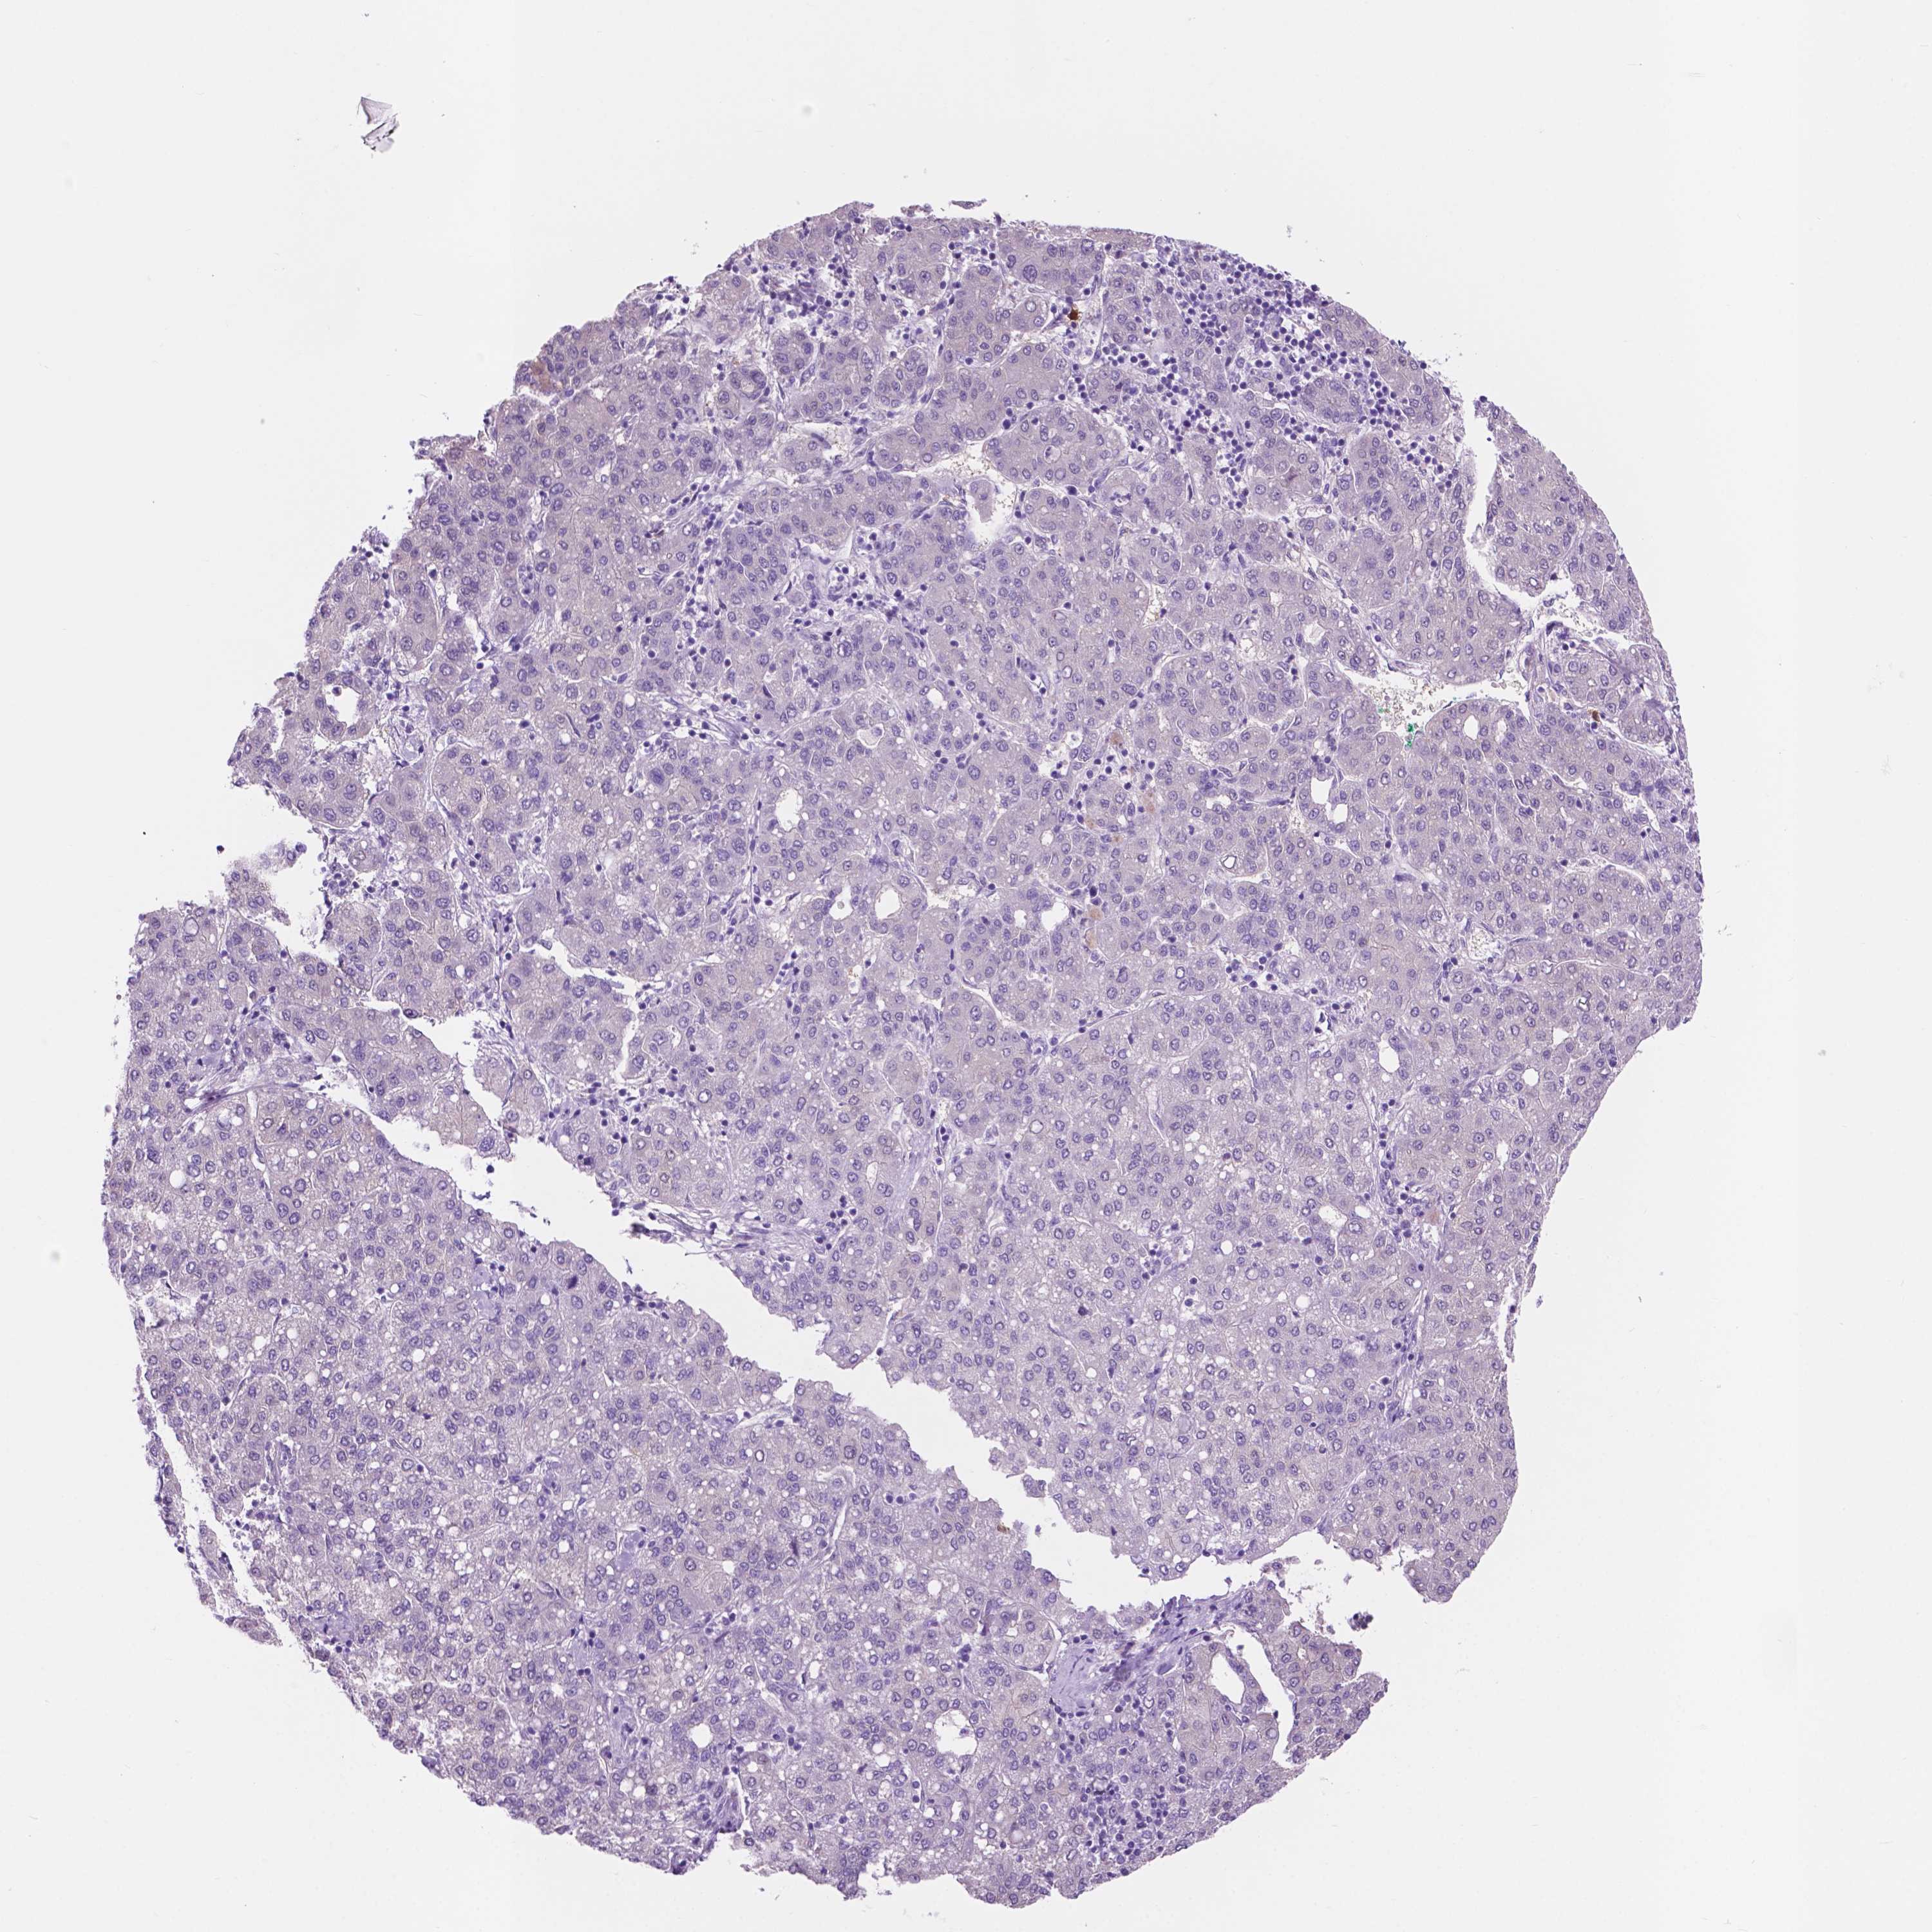

LIVER CANCER - Protein expressioni

A mouse-over function shows sample information and annotation data. Click on an image to view it in a full screen mode. Samples can be filtered based on level of antibody staining by selecting one or several of the following categories: high, medium, low and not detected. The assay and annotation is described here.

Note that samples used for immunohistochemistry by the Human Protein Atlas do not correspond to samples in the TCGA dataset.

Antibody stainingi

Antibody staining in the annotated cell types in the current human tissue is reported as not detected, low, medium, or high, based on conventional immunohistochemistry profiling in selected tissues. This score is based on the combination of the staining intensity and fraction of stained cells.

Each image is clickable and will lead to virtual microscopy that enables deeper exploration of all samples and also displays staining intensity scores, fraction scores and subcellular localization as well as patient and tissue information for each sample.

Antibody HPA039219

Antibody HPA048187

Staining

High

Medium

Low

Not detected

Intensity

Strong

Moderate

Weak

Negative

Quantity

>75%

75%-25%

<25%

None

Location

Nuclear

Cytoplasmic/membranous

Cytoplasmic/membranous,nuclear

Cholangiocarcinoma

Carcinoma, Hepatocellular, NOS